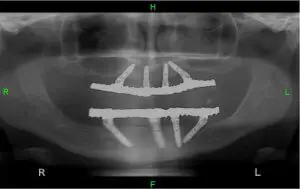

На фотографии, что перед вами, можно увидеть,

как выглядит система из четырех имплантатов которые имплантированных в нижнюю и верхнюю челюсти пациента: